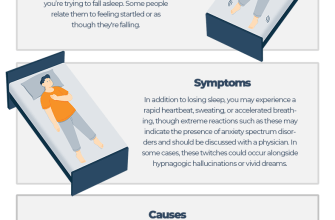

Jerking movements, also known as involuntary movements